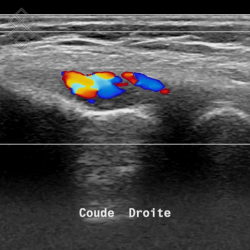

Échographie du Coude

La durée de l'examen est d'environ 20 minutes. Il est indolore et est réalisé par un médecin radiologue.